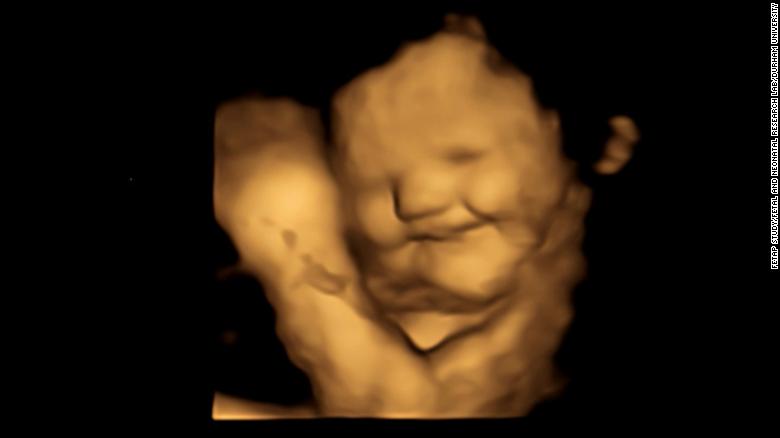

Τα έμβρυα παίρνουν πιο «γελαστό πρόσωπο» στη μήτρα όταν εκτίθενται στη γεύση των καρότων που καταναλώνει η μητέρα τους και «πιο θλιμμένη έκφραση» όταν εκτίθενται στη λαχανίδα (κέιλ), σύμφωνα με μελέτη που δημοσιεύθηκε στο περιοδικό Psychological Science.

Αφού περίμεναν 20 λεπτά μετά την κατανάλωση, οι γυναίκες υποβλήθηκαν σε 4D υπερηχογραφήματα, τα οποία συγκρίθηκαν με 2D εικόνες των εμβρύων.

Το τράβηγμα της γωνίας των χειλιών, που υποδηλώνει χαμόγελο ή γέλιο, ήταν σημαντικά υψηλότερο στην ομάδα του καρότου σε σύγκριση με την ομάδα της λαχανίδας και την ομάδα ελέγχου. Ενώ κινήσεις όπως η ανύψωση του άνω χείλους, η ρίψη του κάτω χείλους προς τα κάτω, το πάτημα των χειλιών και ένας συνδυασμός αυτών – που υποδηλώνει ένα πρόσωπο που κλαίει – ήταν πολύ πιο συχνές στην ομάδα της λαχανίδας σε σχέση με τις άλλες ομάδες.